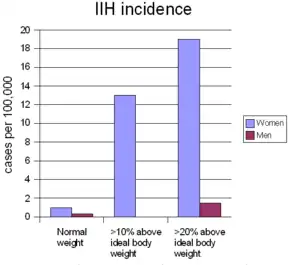

On average, IIH occurs in about one per 100,000 people, and can occur in children and adults. The median age at diagnosis is 30. IIH occurs predominantly in women, especially in the ages 20 to 45, who are four to eight times more likely than men to be affected. Overweight and obesity strongly predispose a person to IIH: women who are more than ten percent over their ideal body weight are thirteen times more likely to develop IIH, and this figure goes up to nineteen times in women who are more than twenty percent over their ideal body weight. In men this relationship also exists, but the increase is only five-fold in those over 20 percent above their ideal body weight.[5]